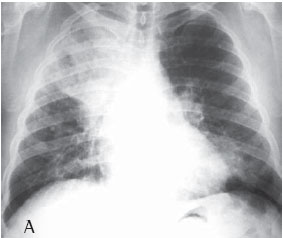

Quanto à classificação radiológica das grandes opacidades na radiografia de tórax verificou-se que: 23 pacientes apresentaram grande opacidade do tipo A (30,7%), 25 do tipo B (33,3%) e 27 do tipo C (36%) (Figuras 1A e 1B). Dos casos analisados, 74 apresentaram massas conglomeradas bilaterais, e apenas 1 apresentou lesão unilateral (Figuras 2A e 2B).

Mais da metade dos pacientes com silicose complicada apresentou na radiografia de tórax grandes opacidades dos tipos B e C, o que denota a gravidade da doença nestes pacientes.